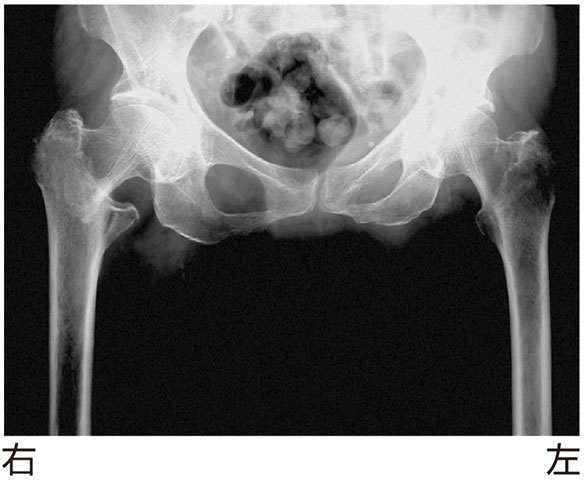

82歳の女性.転倒して右股関節痛を訴えた.エックス線写真を下に示す.疑うべき疾患はどれか.

• 1.股関節脱臼

• 2.坐骨骨折

• 3.大腿骨近位部骨折

• 4.恥骨結合離開

• 5.恥骨骨折

解答: 3